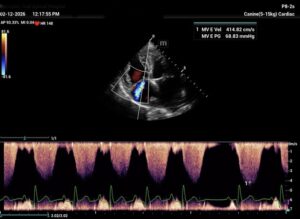

Chronic stage C MVD.TID Pimo and Lasix(high dose), ACEi and Spirono. Doing well. Recheck: Idexx GHP= CBC-NSF ,SDMA 15,BUN 14.1mmol/L, Creat 79umol/L. US: Cornell Indx LVd=1.46(prev2.1), LV septal flattening with diastolic dip,LAAO=2.47,Evel1.45m/s, TVregPG-68mmHg,HV distension-mod ascites.LV and LA underloading via diuretics and PHT (mild PHT past).PHT more pre vs post cap based on small LVsize? Consider Sildenafil/L Arg.Concerned about developing L CHF.Is CHF less likely adding PDE5i with MVD/PHT in underloaded LV than same scenario with vol overloaded LV at similar staging. MVPG=120.3mmHg

My bad! The TV regurge CW Jpeg submitted was mislabeled as MV E vel and its pressure gradient. Sorry for any confucion.